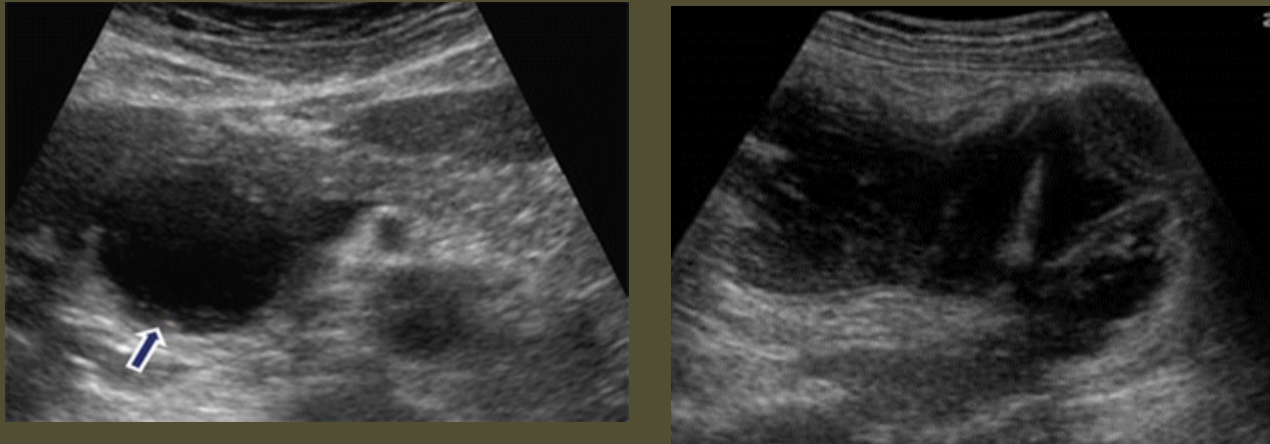

Simple Renal Cyst → common lesion of kidney, fluid-filled sac (benign, Bozniak 1)

2D US: anechoic, well-defined smooth, thin wall, round or ovoid, posterior enhancement

color doppler: avascular

DDX: complex cyst

Complex Renal Cyst → any cyst that is not a simple cyst

2D US: well-defined cystic structure, internal echoes or anechoic, septations, focal hypoechoic inner mural extension, can be hemorrhagic

color doppler: if solid can have vascularity

DDX: malignant tumor, RCC